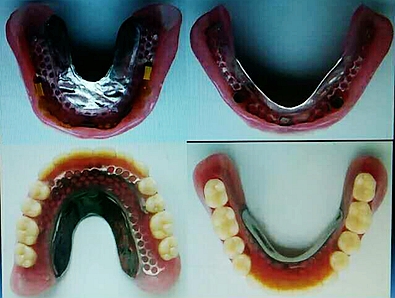

毛國(guó)斌種植病例——群討論分享